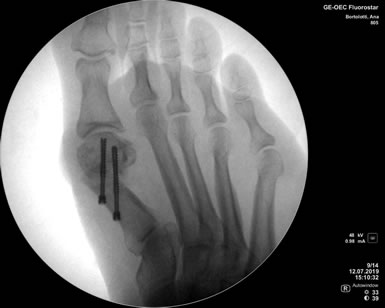

La cirugía Percutánea del pie, también conocida como cirugía MIS (Minimal Incision Surgery), permite realizar procedimientos quirúrgicos a través de pequeñas incisiones en la piel sin gran exposición ni trauma de tejidos.

De esta forma se disminuye el riesgo de complicaciones, como las lesiones de partes blandas, las infecciones y se obtienen menores tiempos operatorios, disminuyendo el dolor y acelerando la vuelta a la vida habitual.

Cirugia Percutanea Dr Masaragian